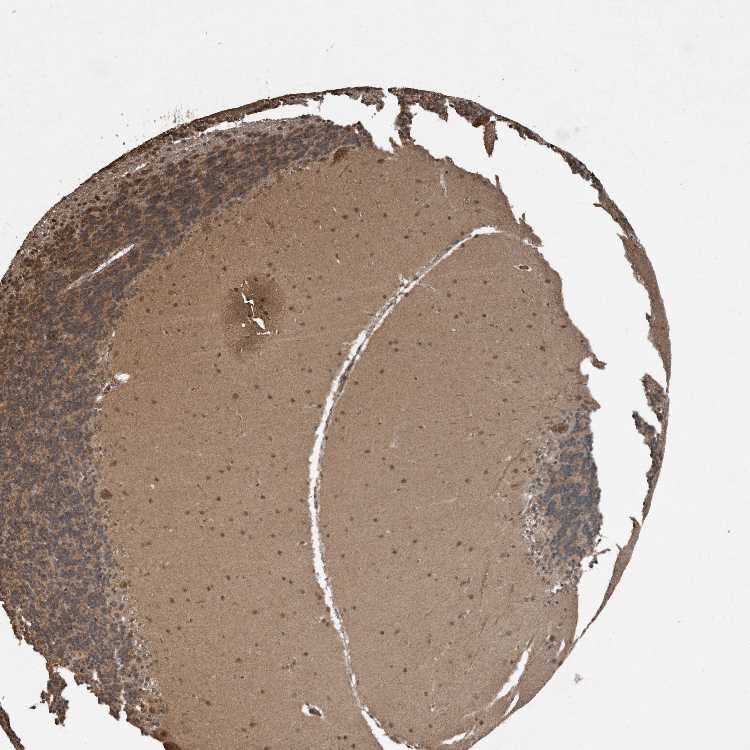

BRAIN CEREBELLUM Show tissue menu

CEREBELLUM - Expression summary

Protein expression

Cerebellumi

On the top, protein expression in current human tissue, based on all annotated cell types, is reported with the units not detected (n), low (l), medium (m) and high (h). Underneath, protein expression in each annotated cell type are reported using the same units.

Protein expression data is based on knowledge-based annotation. For genes where more than one antibody has been used, a collective score is set.

If knowledge-based annotation could not be performed for a gene, no data is displayed here. View antibody staining data further down this page.

h

m

l

n

Cells in granular layer: Not detected

Cells in molecular layer: Low

Purkinje cells: Not detected

CEREBELLUM - Antibody stainingi

Antibody staining in the annotated cell types in the current human tissue is reported as not detected, low, medium, or high, based on conventional immunohistochemistry profiling in selected tissues. This score is based on the combination of the staining intensity and fraction of stained cells.

Each image is clickable and will lead to virtual microscopy that enables deeper exploration of all samples and also displays staining intensity scores, fraction scores and subcellular localization as well as patient and tissue information for each sample.

Antibody HPA018911Antibody CAB025581

Purkinje cells Not detectedMedium

Cells in granular layer Not detectedMedium

Cells in molecular layer LowMedium